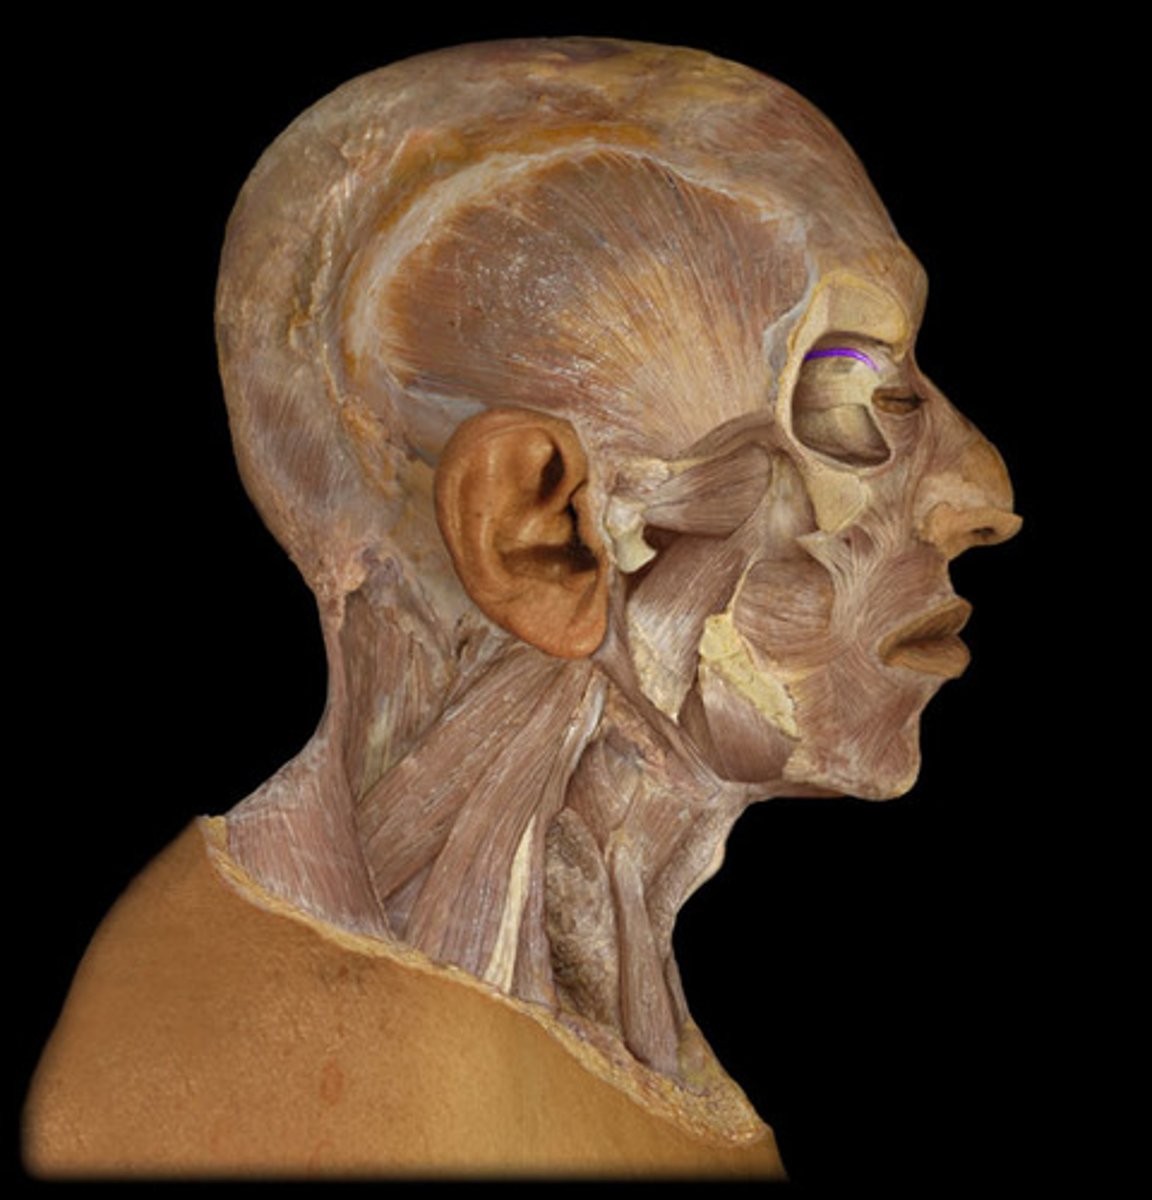

Orbicularis oculi

Levator palpebrae superioris